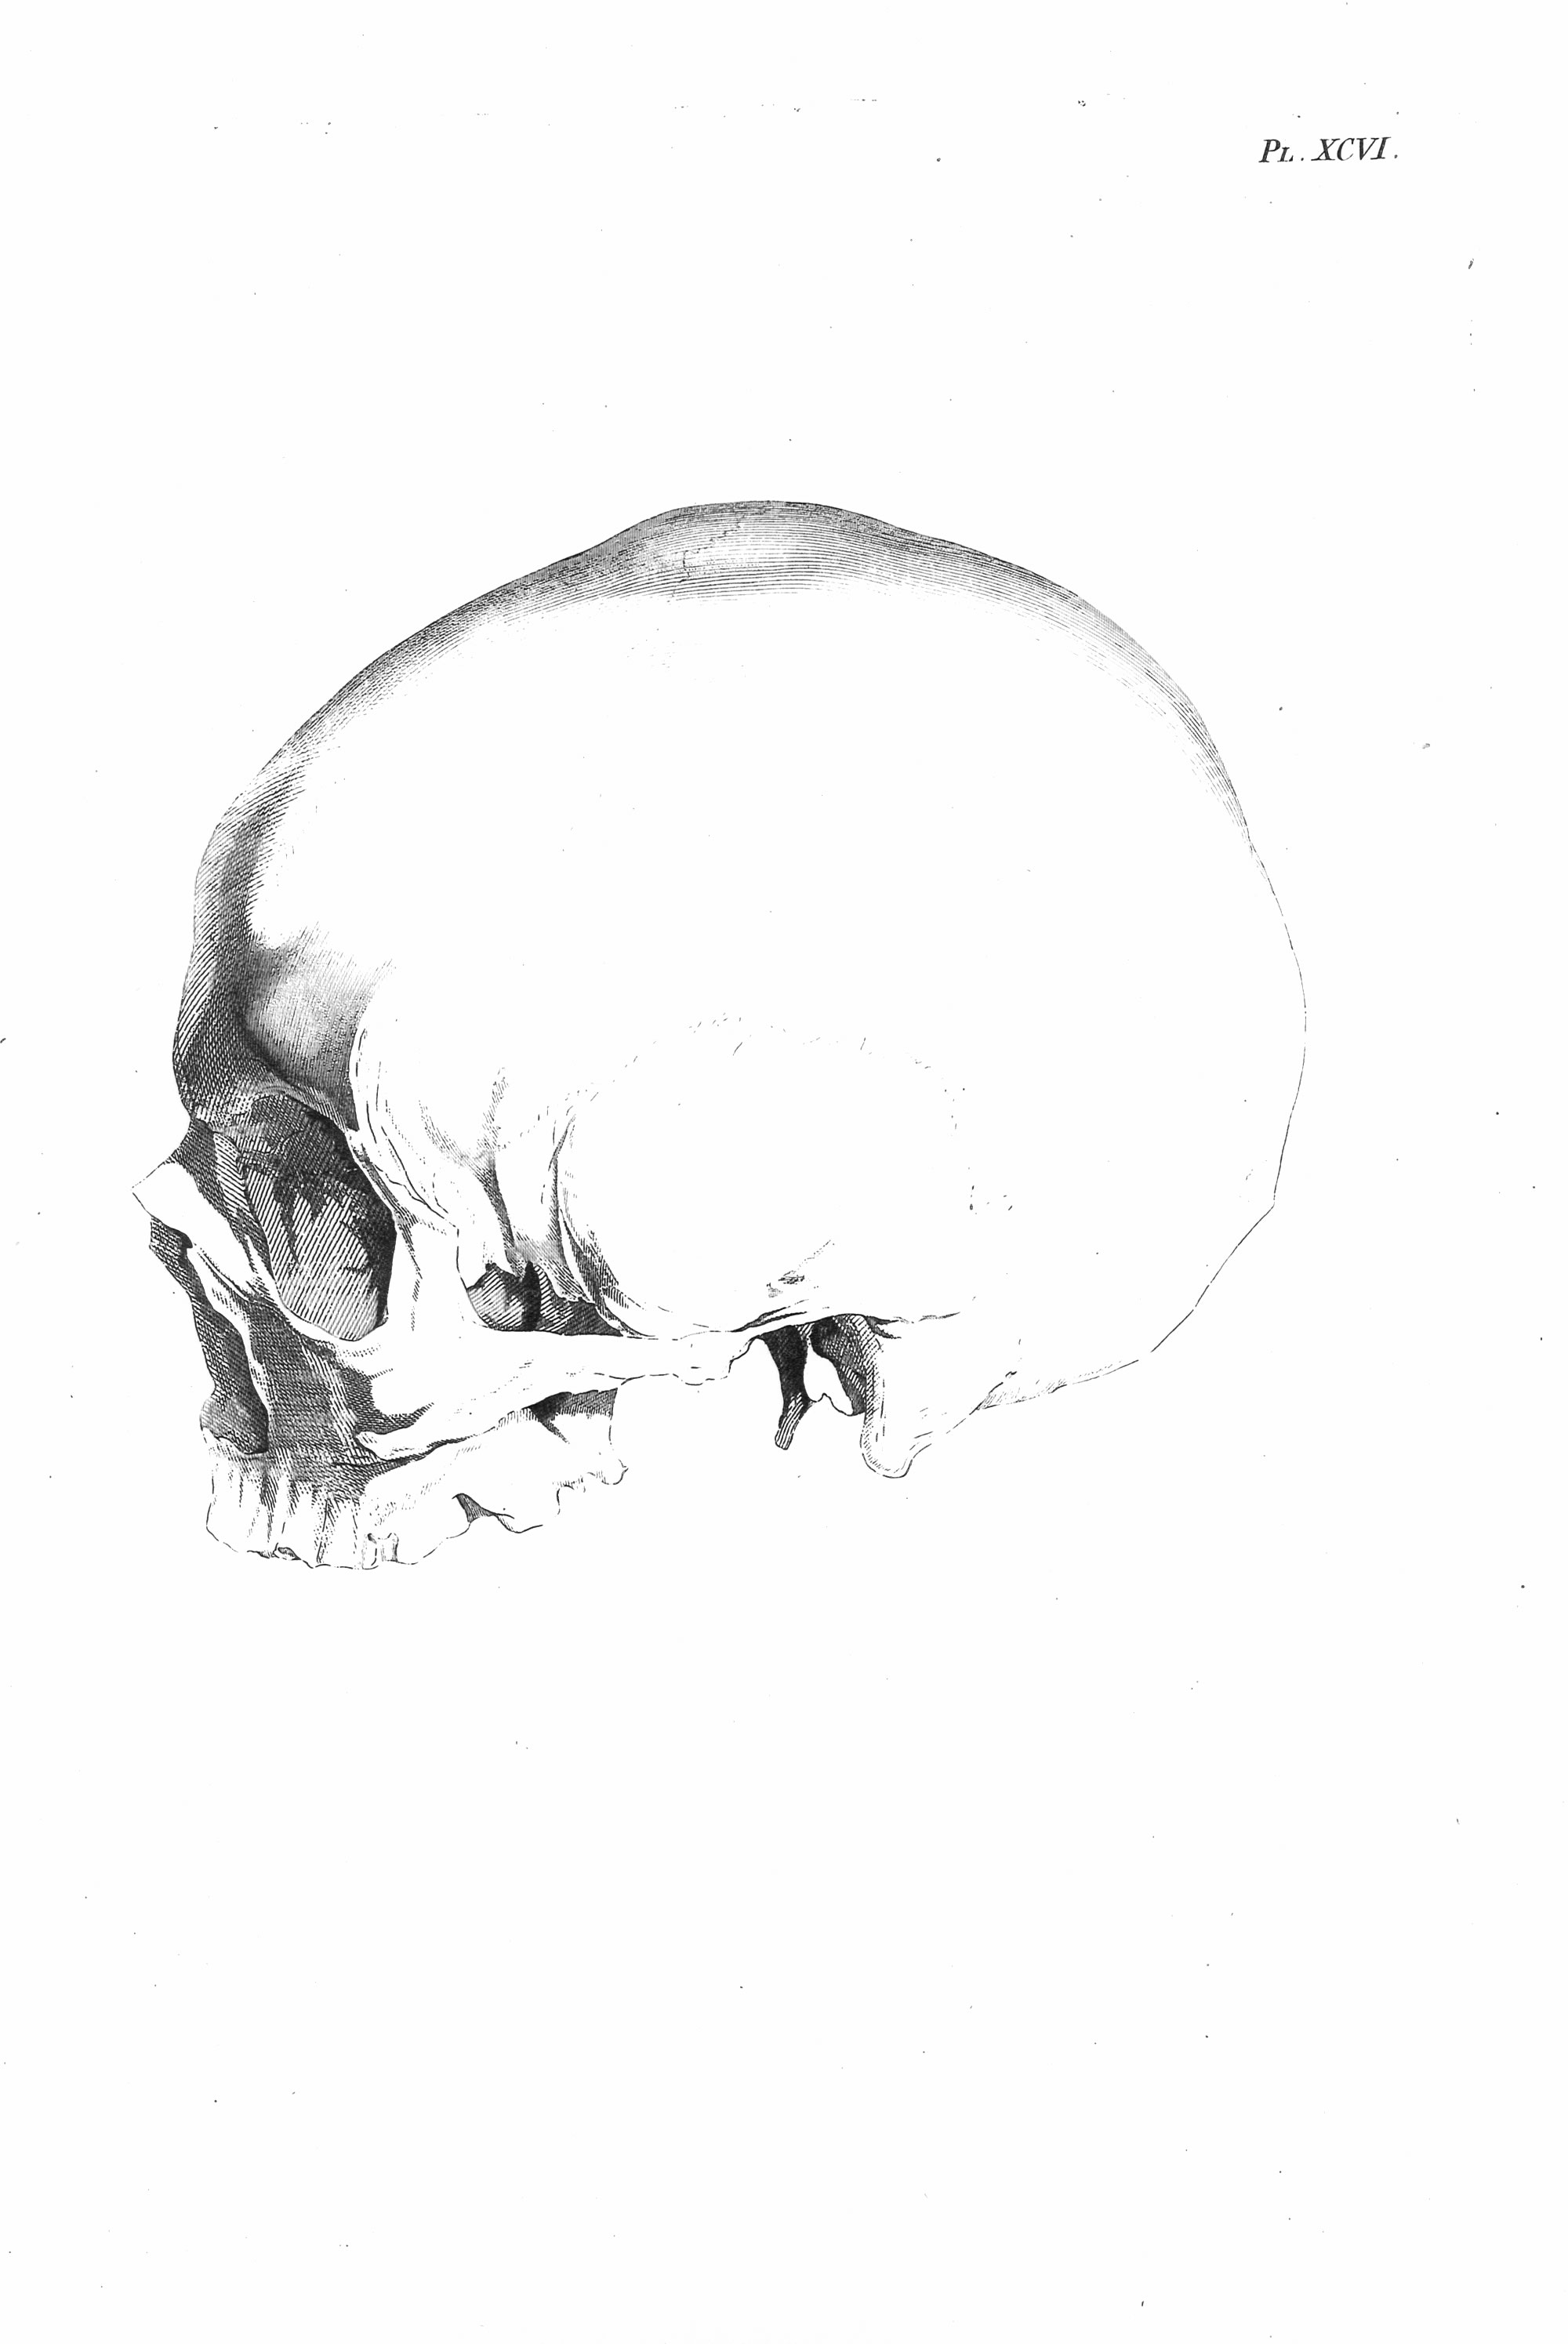

Gall, F. J. (1818). Anatomie et physiologie du système nerveux en général, et du cerveau en particulier, Avec des observations sur la possibilité de reconnoître plusieurs dispositions intellectuelles et morales de l´homme et des animaux, par la configuration de leurs têtes.

Librairie Grecque-Latine-Allemande, Vol. 3, I-XXXV u. 1-379 100 planches.